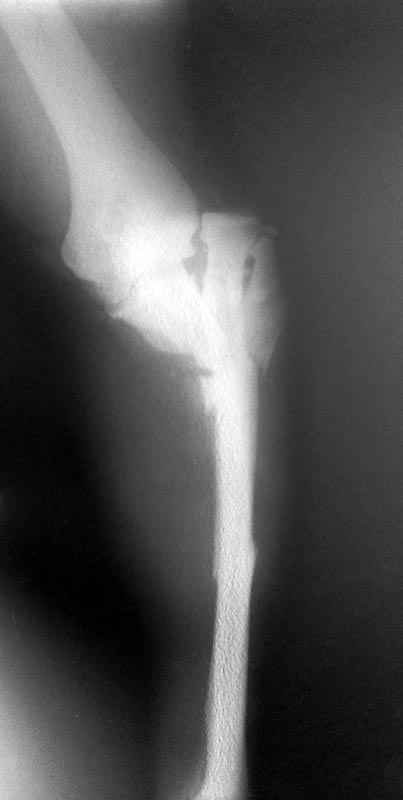

Здравствуйте, уважаемые коллеги.Пацент 36 лет, травма в ДТП открытые переломы. с обширными рваными ранами, которые удалось ушить и, возможно заживут первично. При поступлении- ПХО ран, шов надколенника полукисетами, вправление открытое луча, остеосинтез локтевой кости спицами. Снимки прилагаются. Фото ран - тоже выложу. Прошу предложений о тактике дальнейшего ведения. И хотел бы Ваше мнение о возможности первично фиксации предплечья АВФ и в частности Илизаровским.